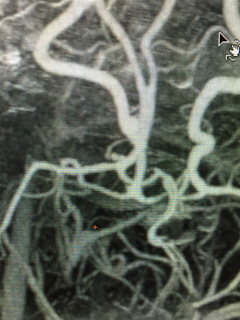

Brain Aneurysm Microsurgery in Dehradun, Uttarakhand

Young Man with Ruptured Brain Aneurysm Microsurgical